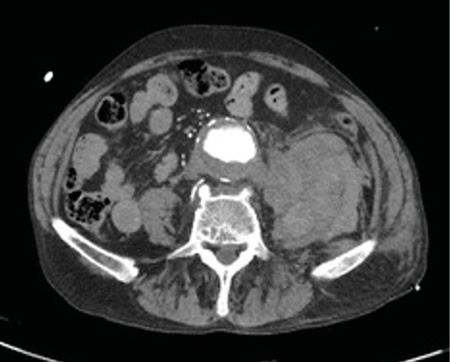

Figura 1

Figura 2